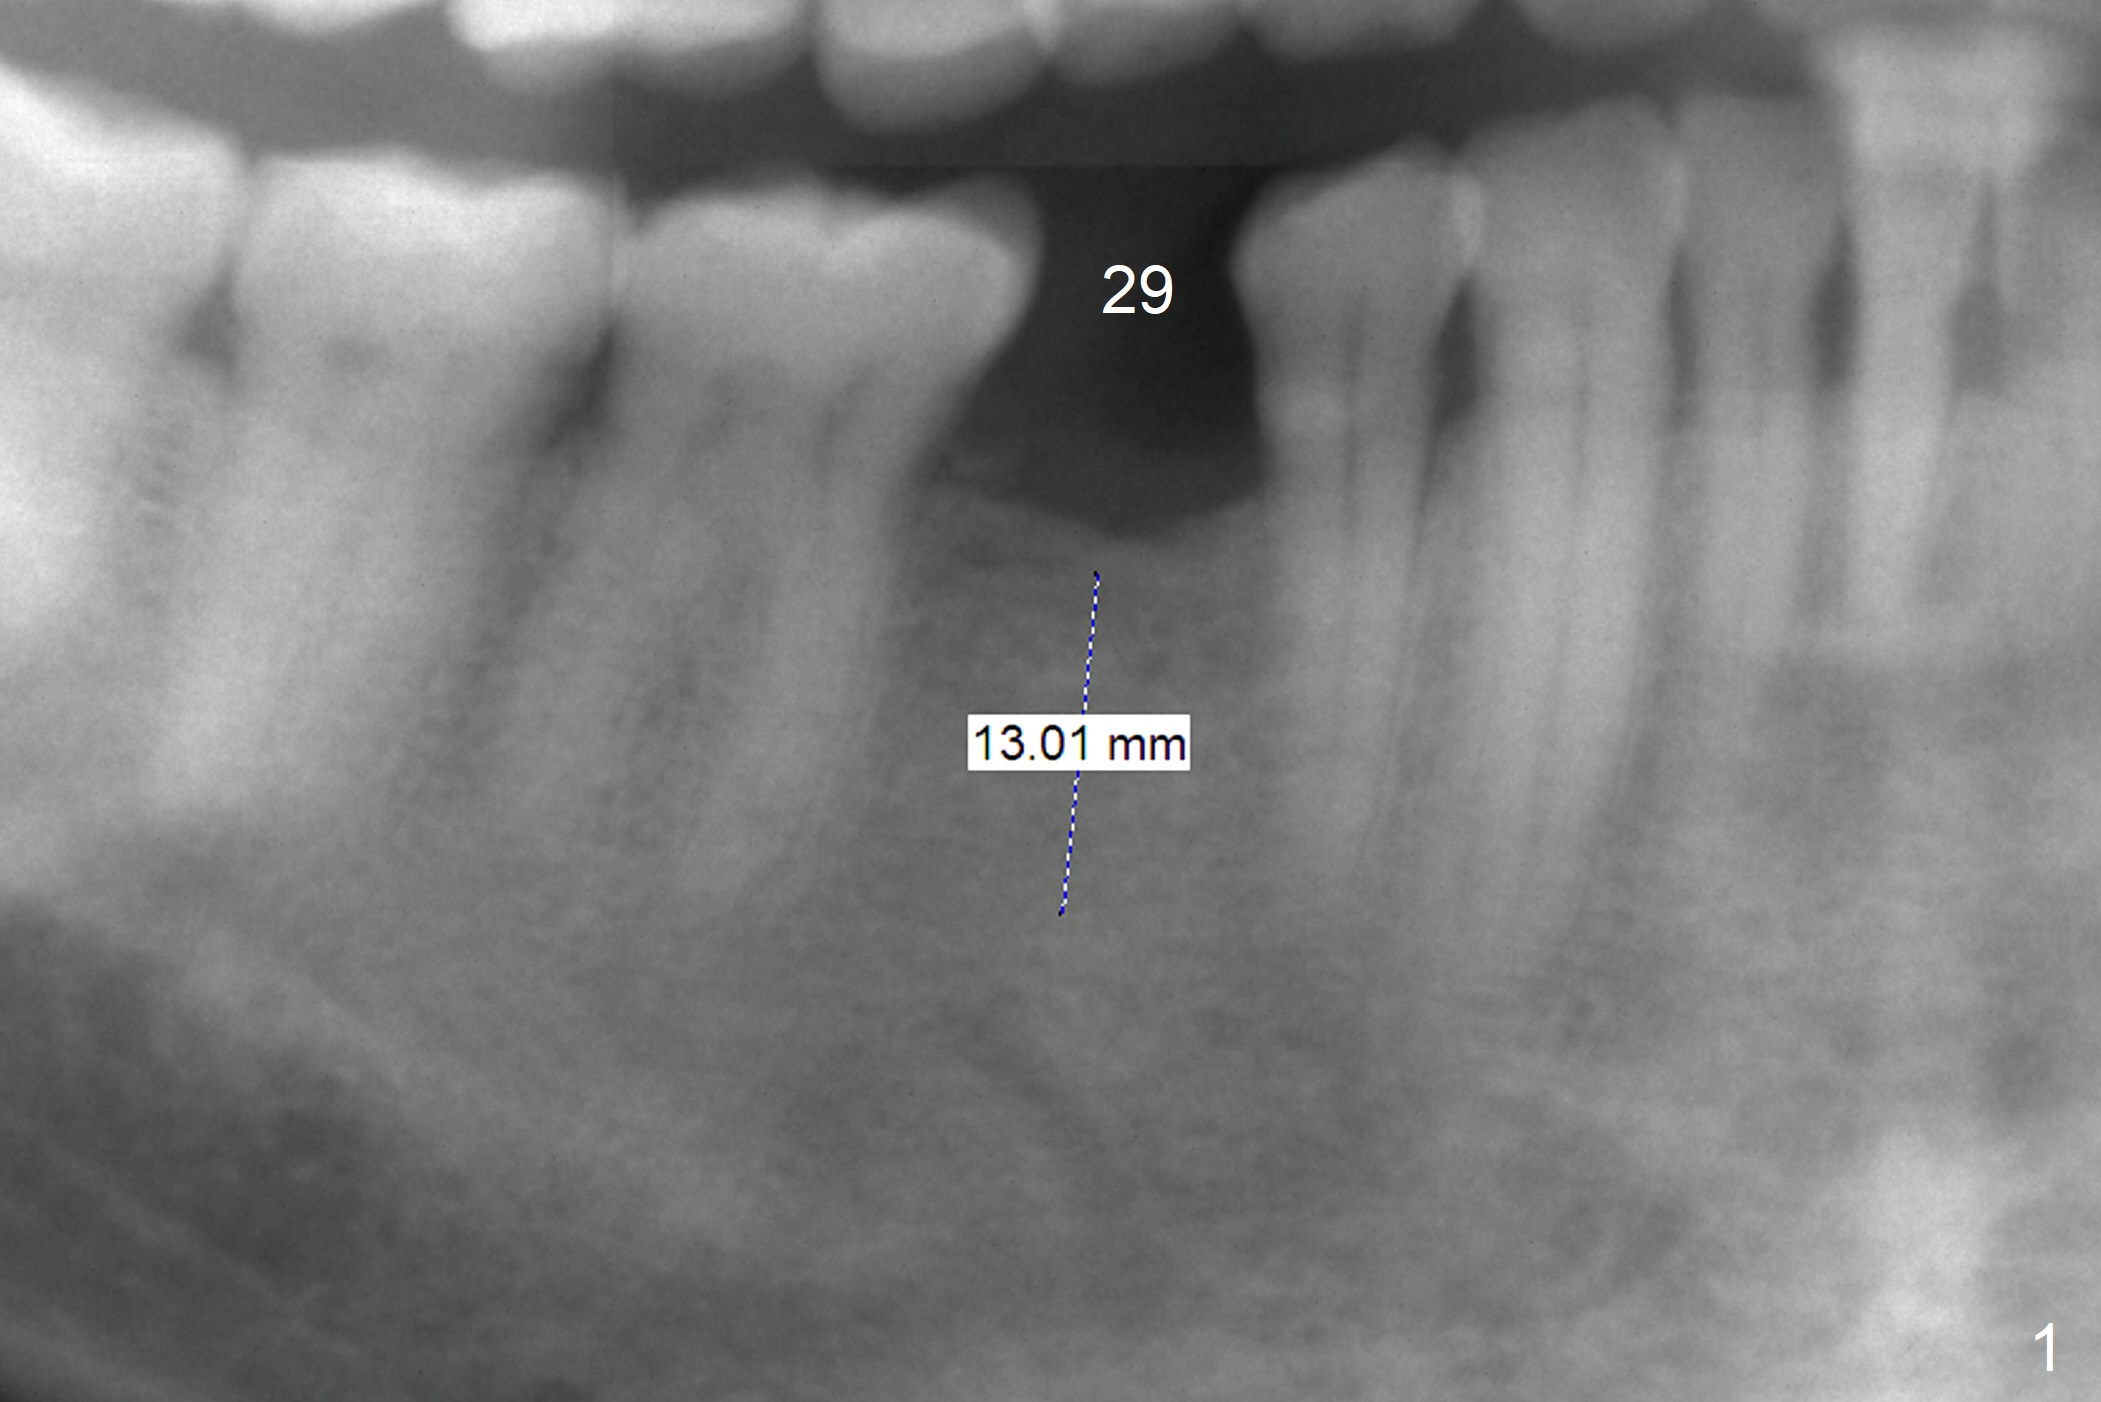

Following implants at #20 and 14, the 56-year-old man will return to clinic for the one at #29 (Fig.1). To avoid postop neighboring tooth sensitivity related to the underlying Mental Loop, the implant to be placed at the premolar area should be distinct clearance from the neurovascular structure. If the ridge turns out to be narrow, either reduce the ridge and/or use a 1-piece implant.